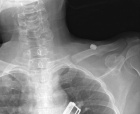

S.L. - 66 year old woman with a history of sarcoidosis and polycythemia vera with low back pain for two months and acute left shoulder pain after opening a window

Zoom image: Cell stain Cell stain.